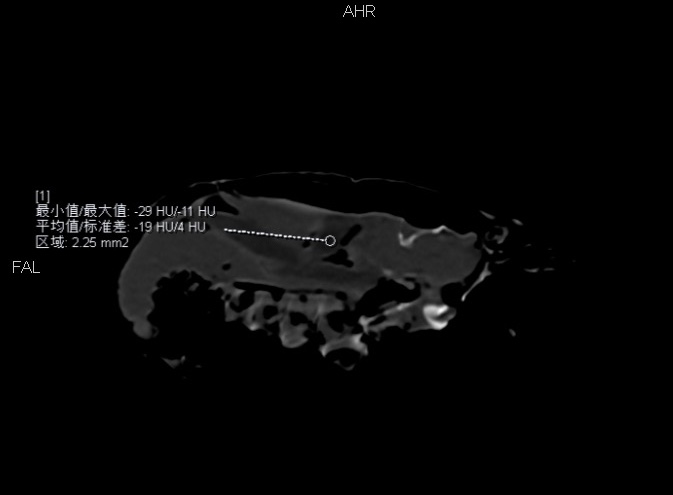

我们平时所说的虾黄对应的是小龙虾的消化腺和性腺,CT 测量发现,这部分密度角相对较低,说明含有脂肪。而颜色偏灰黑的部分多为胃及胃内容物,这部分不能食用,不小心吃到嘴里自然味道欠佳。

小龙虾的消化腺相对密度较低,说明含有脂肪